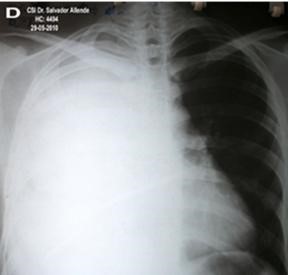

Volver a los detalles del artículo Absceso hepático amebiano con empiema pleural derecho. A propósito de un caso